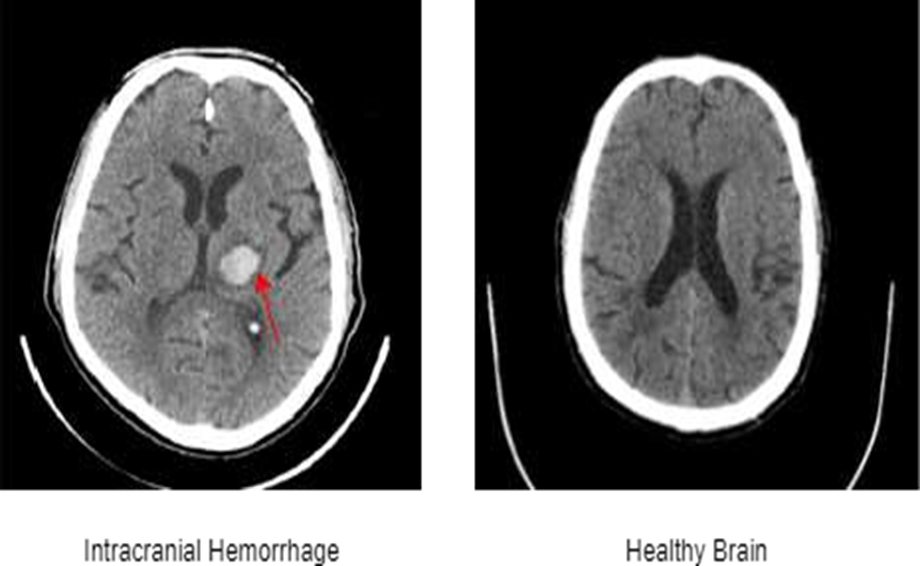

Fig. 1. Sample images of CT scan with Intracranial Hemorrhage (marked with red arrow) and Healthy Brain.